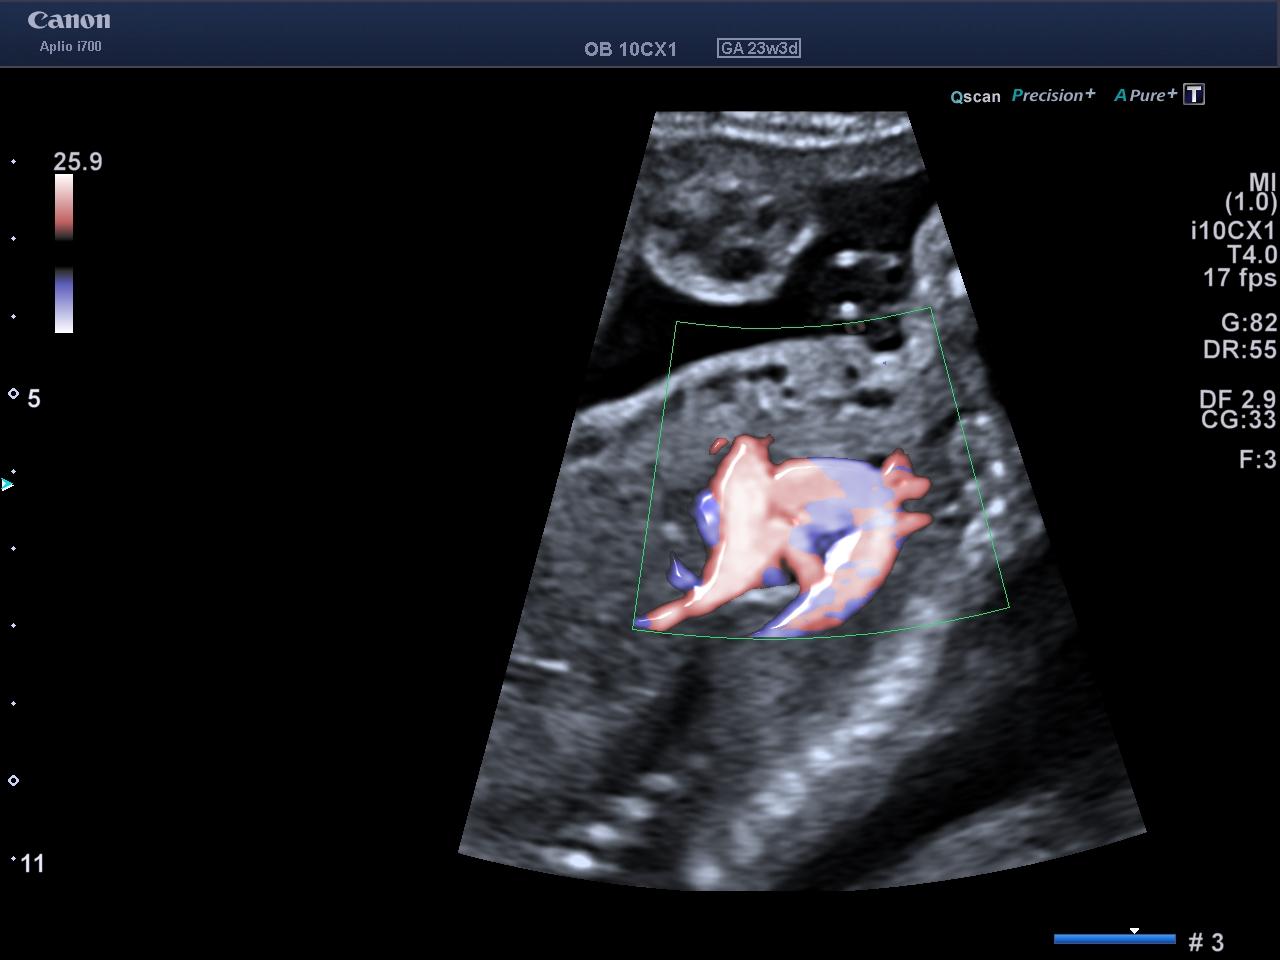

As well as ultrasound, fetal or pediatric echocardiograms also use ultrasound to obtain images.

Pediatric echocardiography aims to examine the heart functionally and morphologically, visualize and document the movements of the heart cavities, evaluate the membrane that surrounds the heart – the pericardium – and detect possible heart pathologies.

For this type of assessment, images are obtained in a single dimension – M-Mode – or in two dimensions – 2D.

This test can also be used to determine the speed and direction of the blood in the heart, as well as its performance in blood circulation – Doppler.